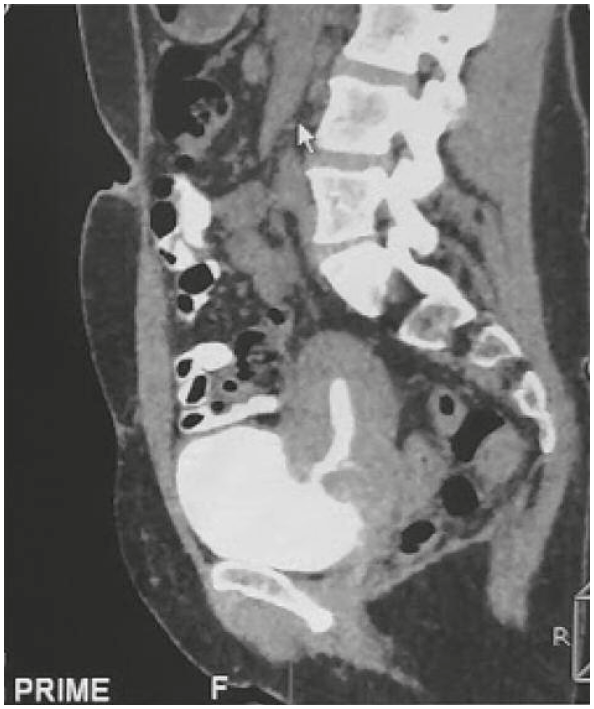

Пациентка 43 лет. Через 1 мес после оперативного родоразрешения появилось непроизвольное выделение мочи из влагалища; пациентка использовала 3–5 урологических прокладок в день. Самопроизвольное мочеиспускание присутствовало. Изначально симптомы расценены как проявление стрессового недержания мочи. Однако при осмотре заподозрен пузырно-влагалищный свищ, рекомендовали оперативное лечение по прошествии 4 мес с момента появления симптомов. Пациентка обратилась за вторым мнением в МЦ «Авиценна», Новосибирск. Детальное изучение анамнеза и жалоб, отсутствие свищевого отверстия на стенке влагалища позволили отвергнуть первичный диагноз и заподозрить пузырно-маточный свищ. Выполнена МСКТ с болюсным контрастированием. В отсроченную фазу визуализировались МП, полость матки и свищевой ход между МП и полостью матки (рис. 1).

Рис. 1. МСКТ пациентки. МП достаточного наполнения, просвет контрастирован полностью. Стенки не утолщены. Определяется дефект задней стенки МП размером около 7¥3 мм (сагиттальный × поперечный), с наличием свищевого хода протяженностью до 12 мм, сообщающегося с дефектом миометрия в передней стенке тела матки на уровне нижней трети, размером около 4¥7 мм (сагиттальный × поперечный); наиболее вероятно, в области рубца после кесарева сечения. Полость матки заполнена контрастным веществом.

Fig. 1. Patient’s MSCT. The bladder is sufficiently full; the lumen is completely contrasted. The walls are not thickened. There is a defect in the posterior wall of the bladder measuring 7¥3 mm (sagittal × transverse) with a fistulous passage of 12 mm, communicating with a defect in the myometrium in the anterior wall of the uterus at the lower third, measuring about 4¥7 mm (sagittal × transverse); most likely in the area of the scar after a cesarean section. The uterine cavity is filled with a contrast agent.